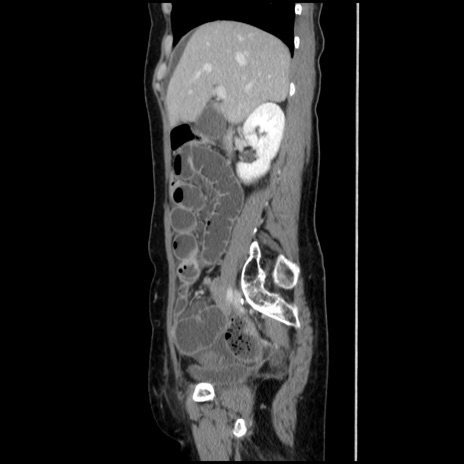

冠状断像

【症例】40歳代 女性

【主訴】上腹部痛、嘔気・嘔吐

【現病歴】約9時間前頃から急に上腹部痛、嘔気、嘔吐が出現。改善しないため救急要請。

【既往歴】子宮頚癌(広汎子宮全摘術、放射線療法)、腸閉塞

【身体所見】腹部:平坦、軟、腸雑音亢進、上腹部を中心に腹部全体に圧痛あり。

【データ】WBC 8400、CRP 0.03